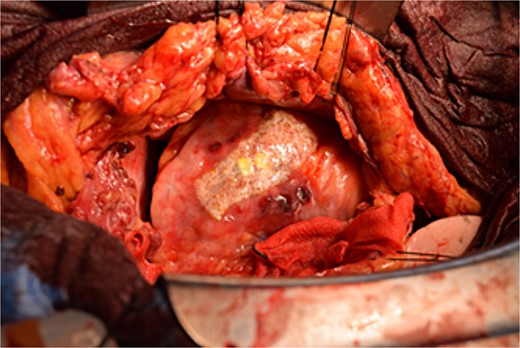

Immediately prior to surgery, he suffered cardiac arrest requiring cardiopulmonary resuscitation but recovered quickly, and a median sternotomy was performed expeditiously. Fortunately, no injury to the retrosternal gastric tube occurred. The gastric tube was pushed into the right thorax to expose the pericardial surface. A pericardial hematoma was observed, and pericardiotomy relieved the tamponade. Removal of the hematoma revealed a 5 mm aneurysm in the peripheral right ventricular branch with pulsatile bleeding (Fig. 4). Hemostasis was achieved using horizontal mattress suturing between the central and peripheral areas of the aneurysm without bypass grafting to the right ventricular branch artery by cardiac surgeon. In addition, TacoSeal® (CSL Behring, Pennsylvania, USA) and Volheal® (KM Biologics, Kumamoto City, Japan) were applied (Fig. 5). The operative time was 133 min, with a blood loss of 1160 ml. Oral intake was initiated on POD 5, and the patient was discharged on POD 22 with an unremarkable postoperative course.

Hemostasis of the coronary artery aneurysm is achieved using horizontal mattress suturing and application of TacoSeal® and Volheal®.